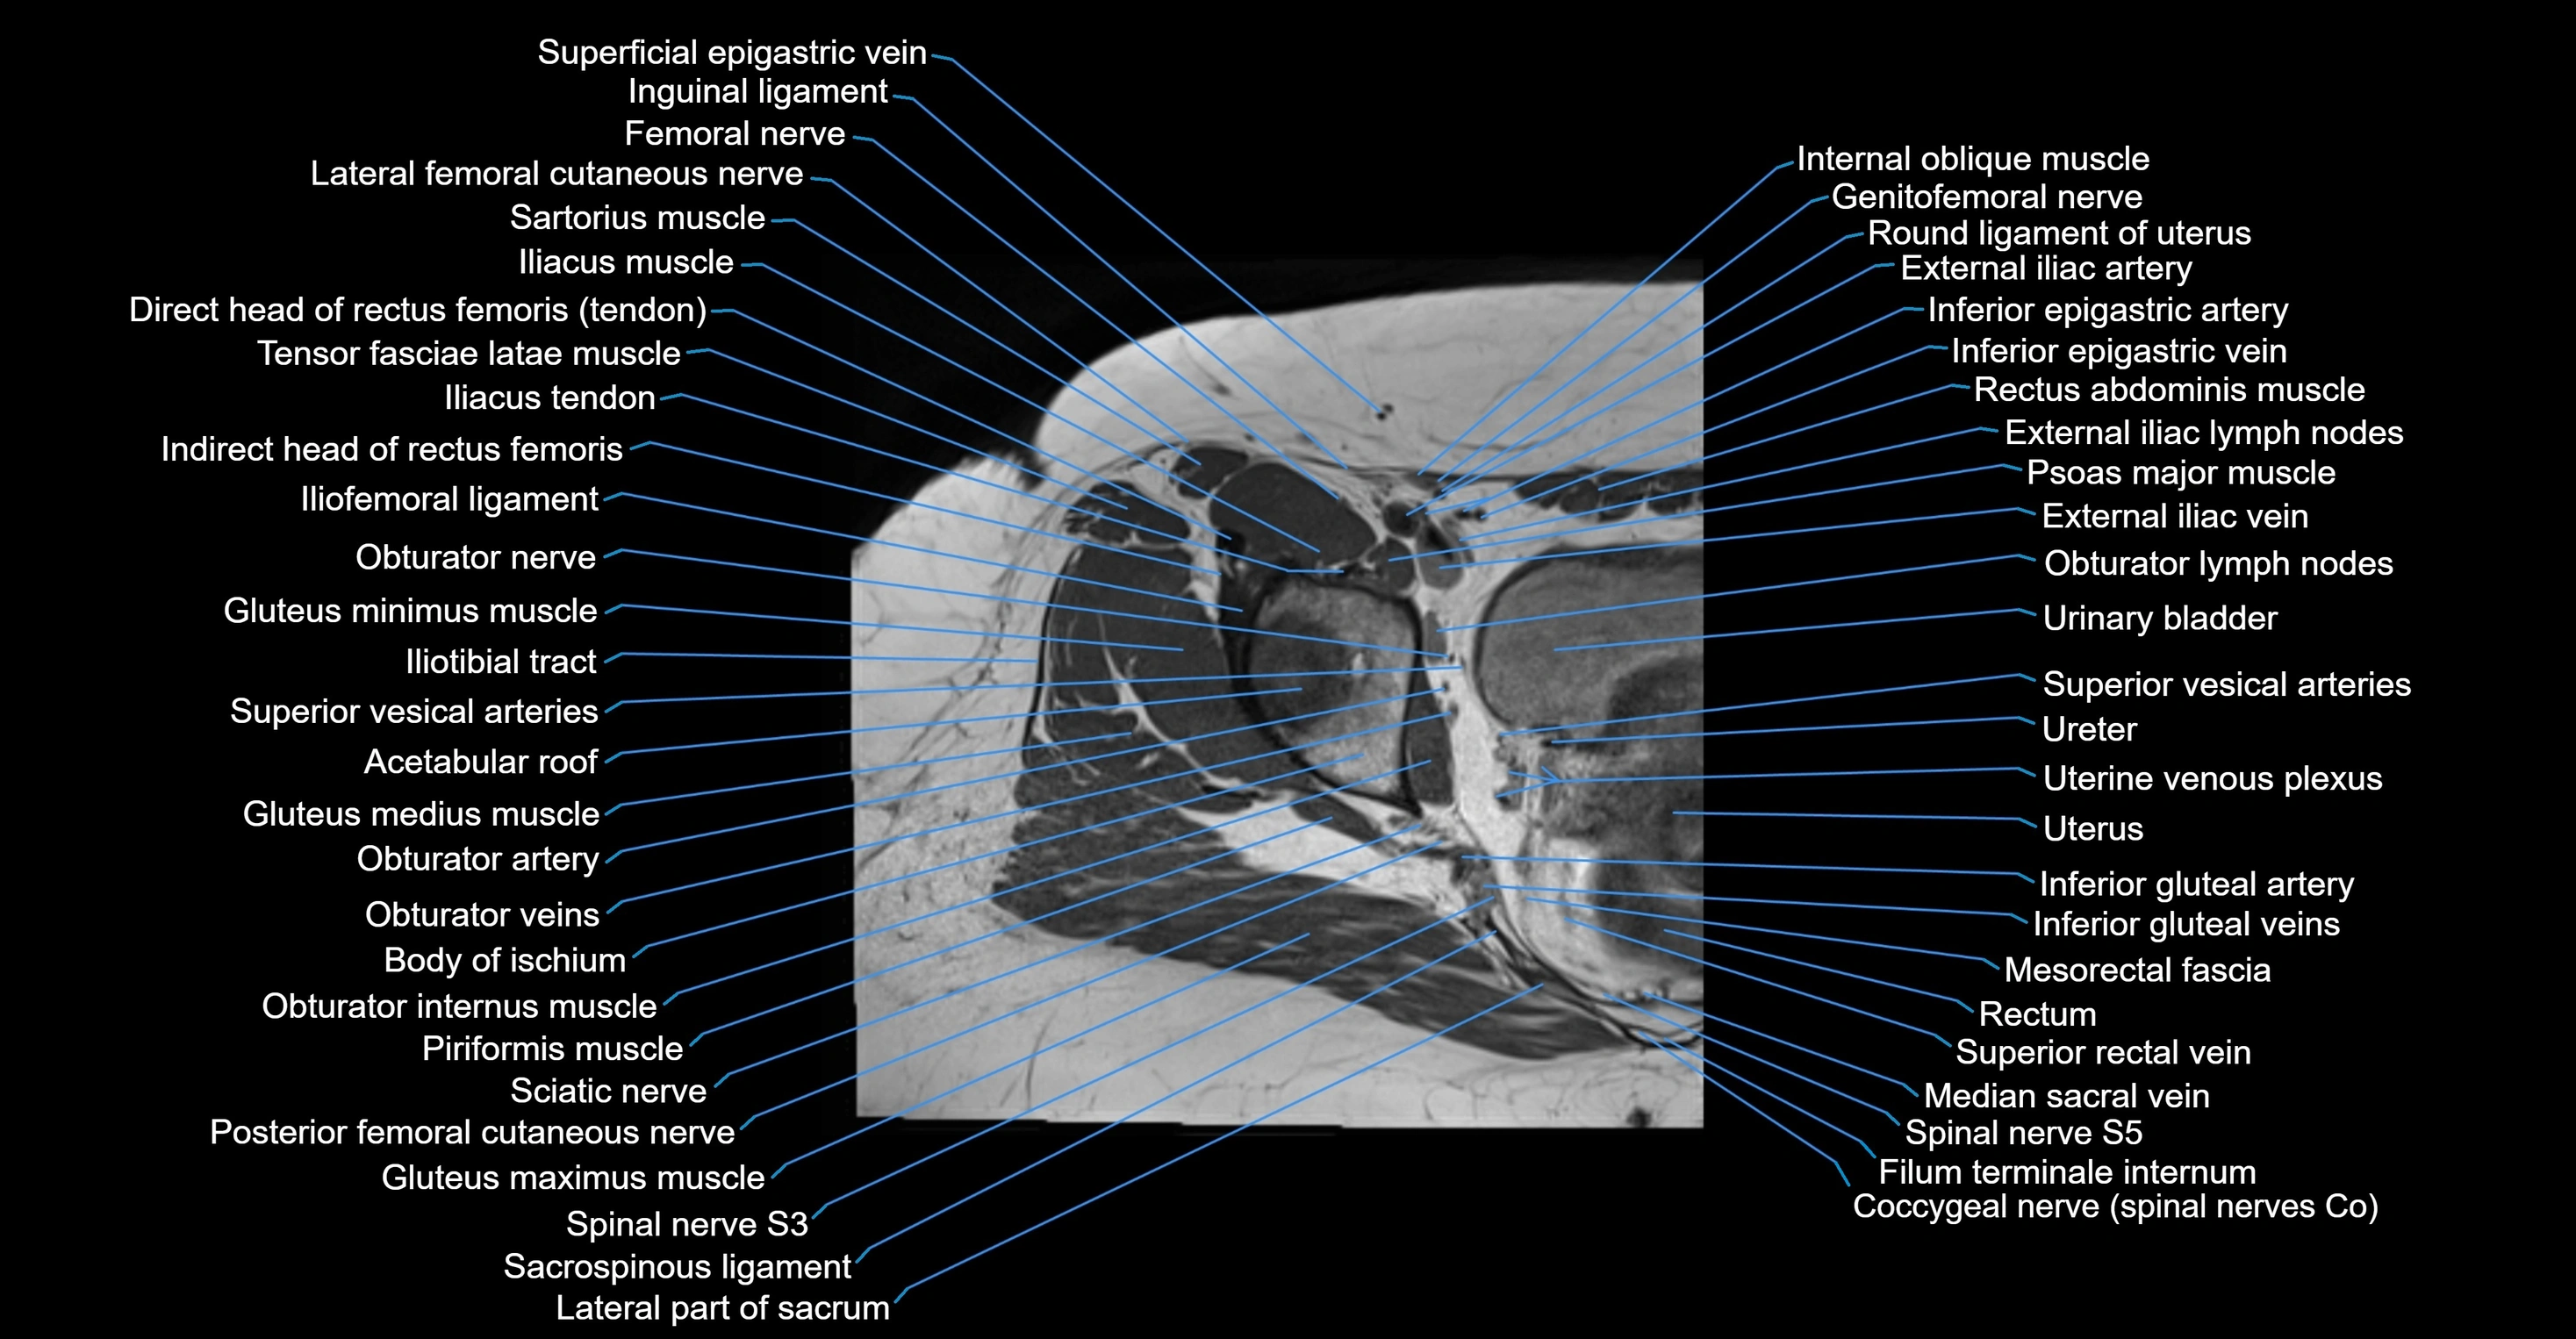

- External iliac lymph nodes

- External iliac vein

- Femoral nerve

- Femoral vein

- Femur

- Genitofemoral nerve

- Gluteus maximus muscle

- Gluteus medius muscle

- Gluteus minimus muscle

- Iliotibial tract

- Ilium bone

- Inguinal ligament

- Lateral femoral cutaneous nerve

- Lumbosacral trunk

- Median sacral vein

- Mesorectal fascia

- Obturator internus muscle

- Obturator lymph nodes

- Obturator vein

- Obturator veins

- Posterior femoral cutaneous nerve

- Rectum

- Round ligament of uterus

- Sacroiliac joint

- Sacrospinous ligament

- Spinal nerve S3

- Spinal nerve S5

- Superior rectal vein

- Superior vesical artery

- Tensor fasciae latae muscle

- Urinary bladder

- Uterine venous plexus

- Uterus